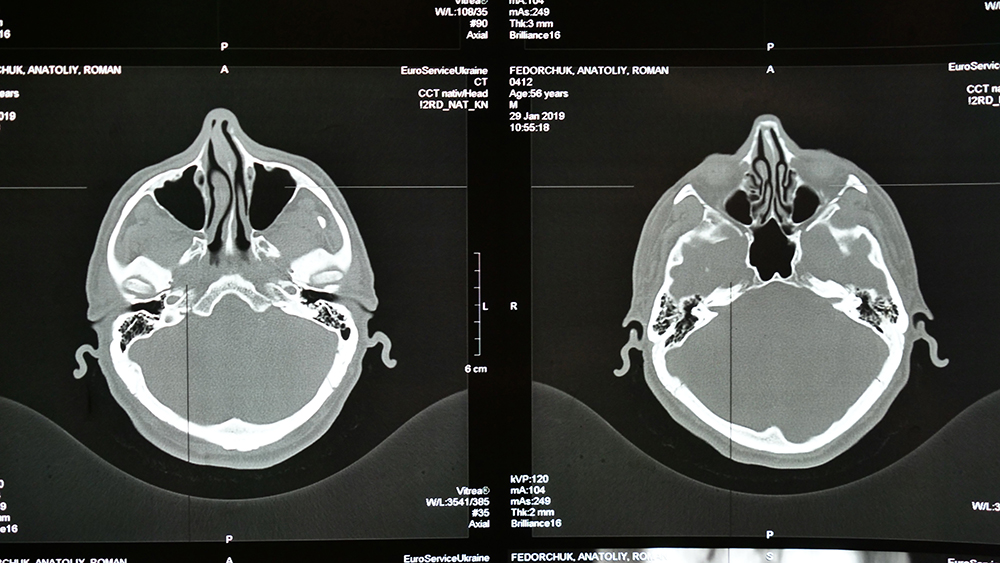

Q: 뇌졸중을 예방하기 위해 어떤 검사를 받아야 하나요?

A: 정기적인 혈압, 혈당, 콜레스테롤 검사를 받는 것이 중요합니다. 필요시 뇌 MRI나 CT 스캔을 통해 상태를 확인할 수 있습니다.